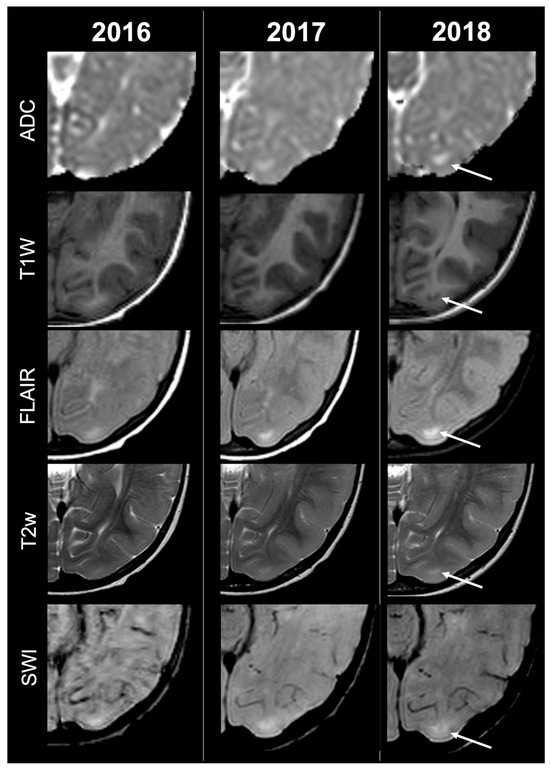

Concerning total lesion count, the interobserver agreement was excellent, with an ICC of 0.91 (95% CI: 0.87–0.95). At baseline, the total number of CTs identified across the cohort was 918 (mean ± SD = 16.1 ± 12.4), whereas at the last available MRI follow-up, the overall count increased to 1070 (mean ± SD = 18.8 ± 13.3), corresponding to a net gain of 152 CTs, equal to a relative variation of +17%. When stratified by tuber type, distinct trajectories were observed over time. Type A CTs, which were relatively abundant at diagnosis (N = 303, mean ± SD = 5.3 ± 7.0), decreased to 255 (mean ± SD = 4.5 ± 5.9) at follow-up, yielding a reduction of 48 lesions (−16%). Conversely, type B CTs showed an opposite trend, increasing from 438 (mean ± SD = 7.7 ± 8.4) at baseline to 556 (mean ± SD = 9.8 ± 8.6) at follow-up, corresponding to a net increase of 118 tubers (+27%). An example of MRI signal evolution from tuber A to tuber B is shown in Figure 1. Similarly, type C1 CTs rose from 160 (mean ± SD = 2.8 ± 4.8) to 220 (mean ± SD = 3.9 ± 5.8), with a net gain of 60 tubers (+38%). Type C2 CTs, initially rare at diagnosis (N = 14, mean ± SD = 0.2 ± 0.8), markedly expanded to 33 (mean ± SD = 0.6 ± 1.5), accounting for an increase of 19 CTs (+136%). Finally, type D CTs were only sporadically encountered, with a modest increase from 3 (mean ± SD = 0.1 ± 0.3) to 6 (mean ± SD = 0.1 ± 0.4), equating to a 100% variation. The observed increment of type C2 tubers was attributable almost exclusively to the progressive transformation of pre-existing type B lesions and, more prominently, type C1 lesions, while the increase in type C1 tubers reflected the gradual conversion of both type A and type B CTs that were already detectable at disease onset. An example of MRI signal evolution from tuber B to C1 is shown in Figure 2, while from tuber C1 to C2 in Figure 3. Only in one patient was a type C1 tuber newly identified at follow-up without clear evidence at baseline. In contrast, newly apparent tubers emerging over time but not clearly visible on baseline scans were most frequently represented by type A and type B lesions. Type D tubers were rare overall and were identified in only six lesions from four patients with a particularly high lesion burden; in all but one case they represented the evolution of type A or type B CTs (an example of MRI signal evolution from tuber A to tuber D is shown in Figure 4), while in a single case they were associated with adjacent subtle calcific foci. Overall descriptive data are summarized in Table 1.

Figure 4.

Left parietal tuber transition from type A to D at three different timepoints in a female patient diagnosed with TSC2.